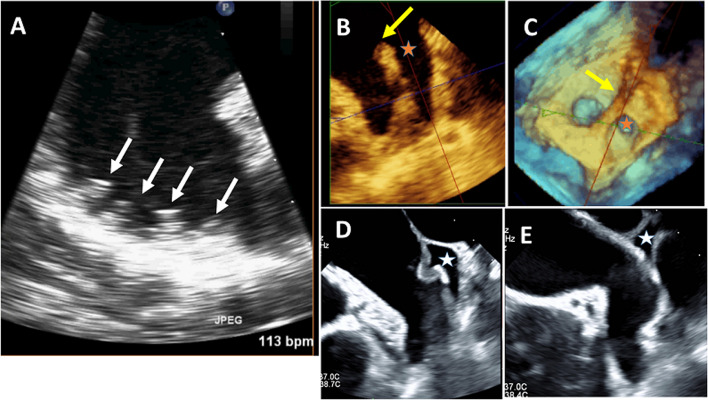

心肌栓塞性中风是心房颤动(房颤)最严重、最危及生命的并发症,12 个月的相关死亡率高达 30%。瓣膜性房颤中约 47% 的血栓和非瓣膜性房颤中 91% 的血栓位于左心房附壁(LAA)。因此,在许多临床情况下,识别或排除 LAA 血栓至关重要。在房颤消融术和 LAA 封堵术等介入手术之前、期间和之后,使用成像模式(尤其是超声心动图)评估 LAA 形态和功能至关重要。这篇综述文章介绍了 LAA 的解剖、生理和病理背景,随后对不同的超声心动图模式进行了评估。其中包括许多实用要点,以提高诊断准确性并尽量减少图像采集和解读过程中的误差。在每个以 LAA 为关键目标的临床场景中,都收集了具体而重要的信息和参数。

Cardioembolic stroke is the most serious and life-threatening complication of atrial fibrillation (AF), with an associated mortality up to 30% at 12 months. Approximately 47% of thrombi in valvular AF and 91% of thrombi in nonvalvular AF are localized in the left atrial appendage (LAA). Therefore, identification or exclusion of LAA thrombi is critical in many clinical situations. It is essential to assess LAA morphology and function using imaging modalities (particularly echocardiography) before, during, and after interventional procedures such as AF ablation and LAA occlusion. This review article describes the anatomical, physiological, and pathological background of the LAA, followed by an assessment of different echocardiographic modalities. Many practical points are included to improve the diagnostic accuracy and to minimize errors during image acquisition and interpretation. In each clinical scenario where LAA is the crucial target, specific and essential information and parameters are collected.